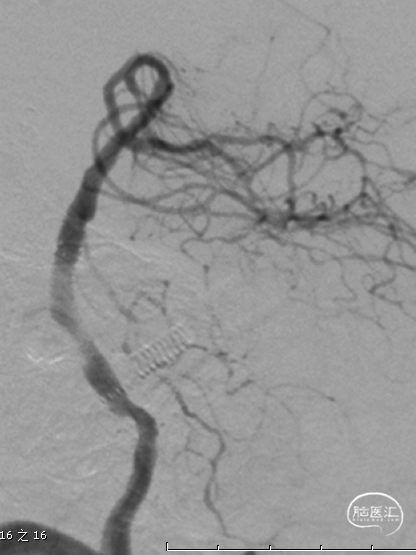

半年后复查造影:支架内无明显再狭窄。椎基底动脉通畅,前向血流mTICI3级。

Synchro微导丝操控性强,非常适合通过此类次全闭塞病变;Neuroform EZ支架经导管释放,技术简单,容易操作;支架的开环设计,保证了在迂曲血管里的良好的贴壁性。